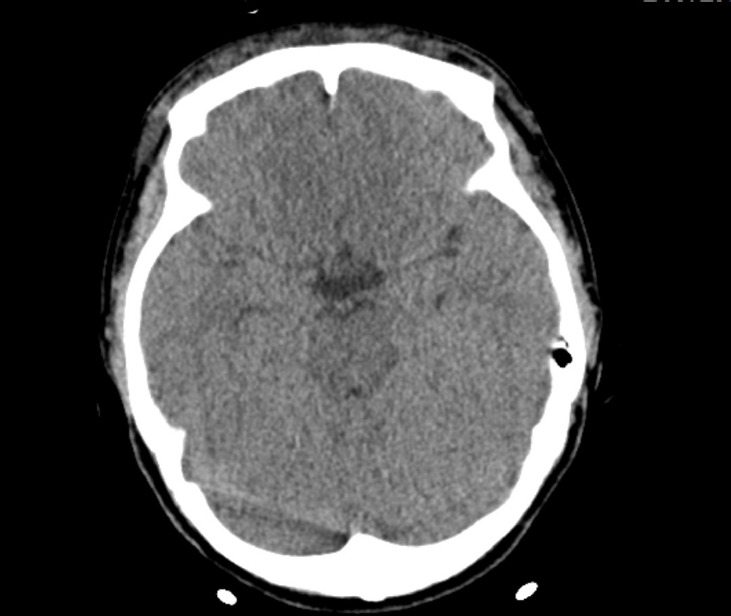

Cardiac compression is the most crucial component of successful cardiopulmonary resuscitation (CPR). However, CPR procedure poses a risk of complications, even when CPR providers perform cardiac compressions as recommended. Reports indicate that solid organ injuries, including liver injuries, occur with an incidence of about 0.6% to 3%. In this particular case, a 25-year-old woman was found hanged in her apartment. She was transported to a nearby hospital where CPR was administered for approximately 30 minutes until she was resuscitated. Subsequently, an abdomen-pelvis computed tomography scan revealed a liver injury. The location of the liver injury, between the sternum and spine, suggested it was a compression injury caused by CPR. There was no evidence of extravasation or active bleeding; thus, conservative management was chosen for the liver injury. By hospital day 4, the patient's pupil reflex had completely disappeared. Electroencephalography showed generalized attenuation, indicating severe global brain damage. Liver injury is a relatively rare post-CPR complication, with an incidence of 0.6% according to a retrospective analysis of a cardiac arrest registry. The liver is partially situated between the sternum and spine. The end of the sternum is shaped like an inverted triangle, resembling a sword. Therefore, if the CPR provider's hands are placed too low or excessive pressure is applied, the sternum can injure the left liver. Blood loss from liver injuries could potentially hinder the successful resuscitation of patients. In this case, had there been no blood loss from the liver injury, the patient might have maintained better cerebral perfusion and function.